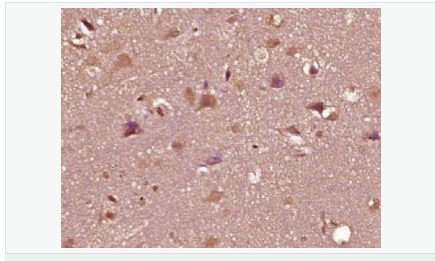

| 產品應用 | WB=1:500-2000 ELISA=1:5000-10000 IHC-P=1:100-500 IHC-F=1:100-500 Flow-Cyt=1ug/Test IF=1:100-500 (石蠟切片需做抗原修復) not yet tested in other applications. optimal dilutions/concentrations should be determined by the end user. |

| 產品介紹 | The androgen receptor gene is more than 90 kb long and codes for a protein that has 3 major functional domains: the N-terminal domain, DNA-binding domain, and androgen-binding domain. The protein functions as a steroid-hormone activated transcription factor. Upon binding the hormone ligand, the receptor dissociates from accessory proteins, translocates into the nucleus, dimerizes, and then stimulates transcription of androgen responsive genes. This gene contains 2 polymorphic trinucleotide repeat segments that encode polyglutamine and polyglycine tracts in the N-terminal transactivation domain of its protein. Expansion of the polyglutamine tract causes spinal bulbar muscular atrophy (Kennedy disease). Mutations in this gene are also associated with complete androgen insensitivity (CAIS). Two alternatively spliced variants encoding distinct isoforms have been described. [provided by RefSeq, Jul 2008] Function: Steroid hormone receptors are ligand-activated transcription factors that regulate eukaryotic gene expression and affect cellular proliferation and differentiation in target tissues. Transcription factor activity is modulated by bound coactivator and corepressor proteins. Transcription activation is down-regulated by NR0B2. Activated, but not phosphorylated, by HIPK3 and ZIPK/DAPK3. [ENZYME REGULATION] AIM-100 (4-amino-5,6-biaryl-furo[2,3-d]pyrimidine) suppresses TNK2-mediated phosphorylation at Tyr-267. Inhibits the binding of the Tyr-267 phosphorylated form to androgen-responsive enhancers (AREs) and its transcriptional activity. Subunit: Binds DNA as a homodimer. Part of a ternary complex containing AR, EFCAB6/DJBP and PARK7. Interacts with HIPK3 and NR0B2 in the presence of androgen. The ligand binding domain interacts with KAT7/HBO1 in the presence of dihydrotestosterone. Interacts with EFCAB6/DJBP, PELP1, PQBP1, RANBP9, RBAK, SPDEF, SRA1, TGFB1I1, ZNF318 and RREB1. Interacts with ZMIZ1/ZIMP10 and ZMIZ2/ZMIP7 which both enhance its transactivation activity. Interacts with SLC30A9 and RAD54L2/ARIP4. Interacts via the ligand-binding domain with LXXLL and FXXLF motifs from NCOA1, NCOA2, NCOA3, NCOA4 and MAGEA11. The AR N-terminal poly-Gln region binds Ran resulting in enhancement of AR-mediated transactivation. Ran-binding decreases as the poly-Gln length increases. Interacts with HIP1 (via coiled coil domain). Interacts (via ligand-binding domain) with TRIM68. Interacts with TNK2. Interacts with USP26. Interacts with RNF6. Interacts (regulated by RNF6 probably through polyubiquitination) with RNF14; regulates AR transcriptional activity. Interacts with PRMT2 and TRIM24. Interacts with GNB2L1/RACK1. Interacts with RANBP10; this interaction enhances dihydrotestosterone-induced AR transcriptional activity. Interacts with PRPF6 in a hormone-independent way; this interaction enhances dihydrotestosterone-induced AR transcriptional activity. Interacts with STK4/MST1. Interacts with ZIPK/DAPK3. Interacts with LPXN. Interacts with MAK. Part of a complex containing AR, MAK and NCOA3. Subcellular Location: Nucleus. Cytoplasm. Note=Predominantly cytoplasmic in unligated form but translocates to the nucleus upon ligand-binding. Can also translocate to the nucleus in unligated form in the presence of GNB2L1. Tissue Specificity: Isoform 2 is mainly expressed in heart and skeletal muscle. Post-translational modifications: Sumoylated on Lys-386 (major) and Lys-520. Ubiquitinated. Deubiquitinated by USP26. 'Lys-6' and 'Lys-27'-linked polyubiquitination by RNF6 modulates AR transcriptional activity and specificity. Phosphorylated in prostate cancer cells in response to several growth factors including EGF. Phosphorylation is induced by c-Src kinase (CSK). Tyr-534 is one of the major phosphorylation sites and an increase in phosphorylation and Src kinase activity is associated with prostate cancer progression. Phosphorylation by TNK2 enhances the DNA-binding and transcriptional activity and may be responsible for androgen-independent progression of prostate cancer. Phosphorylation at Ser-81 by CDK9 regulates AR promoter selectivity and cell growth. Phosphorylation by PAK6 leads to AR-mediated transcription inhibition. Palmitoylated by ZDHHC7 and ZDHHC21. Palmitoylation is required for plasma membrane targeting and for rapid intracellular signaling via ERK and AKT kinases and cAMP generation. DISEASE: Defects in AR are the cause of androgen insensitivity syndrome (AIS) [MIM:300068]; previously known as testicular feminization syndrome (TFM). AIS is an X-linked recessive form of pseudohermaphroditism due end-organ resistance to androgen. Affected males have female external genitalia, female breast development, blind vagina, absent uterus and female adnexa, and abdominal or inguinal testes, despite a normal 46,XY karyotype. Defects in AR are the cause of spinal and bulbar muscular atrophy X-linked type 1 (SMAX1) [MIM:313200]; also known as Kennedy disease. SMAX1 is an X-linked recessive form of spinal muscular atrophy. Spinal muscular atrophy refers to a group of neuromuscular disorders characterized by degeneration of the anterior horn cells of the spinal cord, leading to symmetrical muscle weakness and atrophy. SMAX1 occurs only in men. Age at onset is usually in the third to fifth decade of life, but earlier involvement has been reported. It is characterized by slowly progressive limb and bulbar muscle weakness with fasciculations, muscle atrophy, and gynecomastia. The disorder is clinically similar to classic forms of autosomal spinal muscular atrophy. Note=Caused by trinucleotide CAG repeat expansion. In SMAX1 patients the number of Gln ranges from 38 to 62. Longer expansions result in earlier onset and more severe clinical manifestations of the disease. Note=Defects in AR may play a role in metastatic prostate cancer. The mutated receptor stimulates prostate growth and metastases development despite of androgen ablation. This treatment can reduce primary and metastatic lesions probably by inducing apoptosis of tumor cells when they express the wild-type receptor. Defects in AR are the cause of androgen insensitivity syndrome partial (PAIS) [MIM:312300]; also known as Reifenstein syndrome. PAIS is characterized by hypospadias, hypogonadism, gynecomastia, genital ambiguity, normal XY karyotype, and a pedigree pattern consistent with X-linked recessive inheritance. Some patients present azoospermia or severe oligospermia without other clinical manifestations. Similarity: Belongs to the nuclear hormone receptor family. NR3 subfamily. Contains 1 nuclear receptor DNA-binding domain. SWISS: P10275 Gene ID: 367 Database links: Entrez Gene: 367 Human Entrez Gene: 11835 Mouse Omim: 313700 Human SwissProt: P10275 Human SwissProt: P19091 Mouse Unigene: 496240 Human Unigene: 39005 Mouse Unigene: 394224 Mouse Unigene: 439657 Mouse Unigene: 9813 Rat Important Note: This product as supplied is intended for research use only, not for use in human, therapeutic or diagnostic applications. AR是一個由917個氨基酸組成的蛋白質,位于雄激素靶組織細胞中或細胞表面上的特異分子部位或結構。 AR在前列腺癌中起著重要的作用,研究表明AR的表達與組織分型形成一定的相關性 ,AR在高分化的腫瘤中表達較多,而在低分化的腫瘤中表達較少。用于前列腺癌的檢測,指導臨床治療,目前可用于乳腺癌、食道癌等各項腫瘤的研究。 |